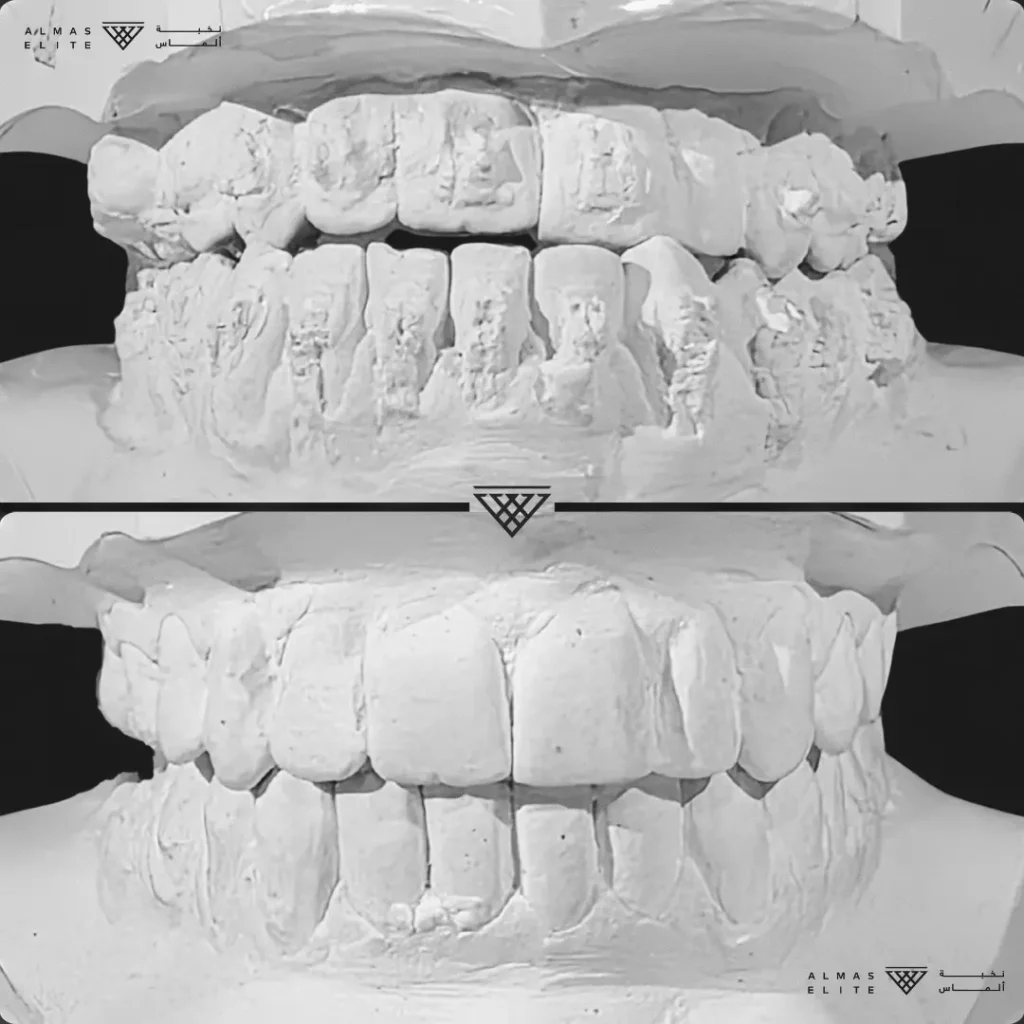

- تشخيص دقيق يشمل الأشعة والتحليل الرقمي للأسنان والفكين.

٢) التقييم والتشخيص الشامل

يشمل صور الأشعة والتحليل الرقمي للأسنان والفكين للوصول إلى تشخيص دقيق.